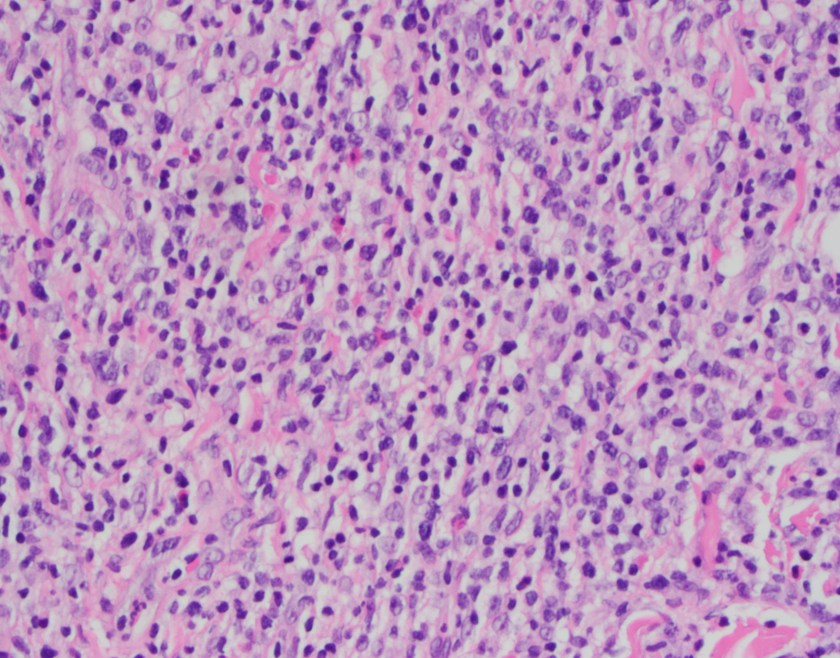

H&E stained sections reveal sheets of large lymphocytes. The lymphoid cells are medium to large in size with irregular nuclear contours and prominent nuclei. Areas of necrosis are prominent. No specific areas of epithelial ulceration are noted. Immunophenotypic characterization of the larger cells reveals positivity for CD20, CD30, CD79a, PAX5, MUM1, Epstein Barr virus encoded RNA (EBER) and a variable Ki-67 proliferation index, which is up to 60-70% in the larger cells, but around 20-30% overall. Only rare cells are positive for BCL-2 and BCL-6. The lymphoma cells are negative for keratin AE1/AE3, CD10, CD4, CD8, CD21, CD23, CD7, CD5, Cyclin D1, CD68, CD56, and CD43. The background T cells express CD5 and CD7 and are a mixture of CD4 and CD8 with CD4 predominance.